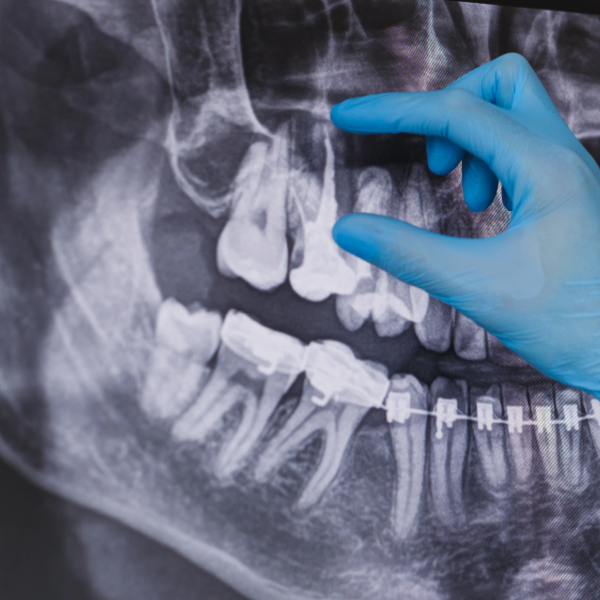

원래 신경치료를 한곳이라 문제가 있는줄 몰랐는데 뿌리에 문제가 있다고 사진을 여러번 찍더라구요.ㅜ.ㅜ

"치아 뿌리 끝에 염증이 생겼다", "수술이나 발치를 해야 한다"는 무서운 얘기였는데요. 그리고 생소한 진단명을 들었습니다.

📌 2. 치근단염(Periapical abscess)이란?

치아 뿌리 끝(치근단)에 세균 감염으로 생긴 염증

- 신경치료(근관치료) 후 재감염